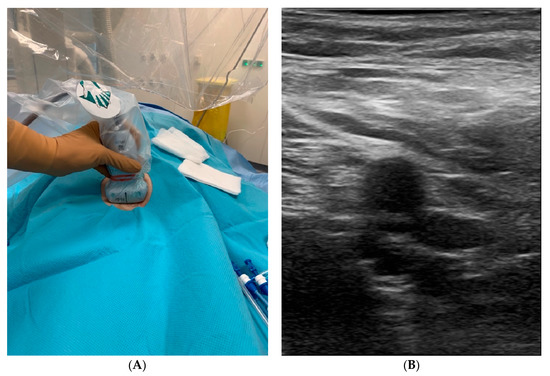

3. Vascular Access by Conventional or UGVP Technique